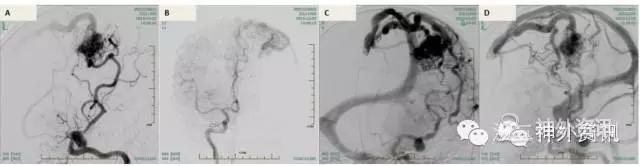

入院后进一步行3D-DSA检查,动静脉畸形主要由左侧大脑中、大脑前动脉分支供血,大小约4cm*3cm(图2)。同时,在3D图像上显示左侧大脑中动脉M2段起始部及中动脉远端入畸形团前的分支上分别可见两枚动脉瘤(图3)。

图2. DSA显示左额顶区动静脉畸形,主要由大脑中、前动脉供血。A、B. 所示动静脉畸形由左侧大脑前、中动脉分支供血;C、D. 显示粗大引流静脉。

图3. 3D-DSA显示动静脉畸形伴多发中动脉动脉瘤。A. 左侧大脑中动脉M2段起始部动脉瘤(绿色箭头)及中动脉远端入畸形团前分支上动脉瘤(红色箭头);B. 显示左侧大脑中动脉M2段起始部动脉瘤(绿色箭头);C. 显示中动脉远端入畸形团前分支上动脉瘤(红色箭头)。